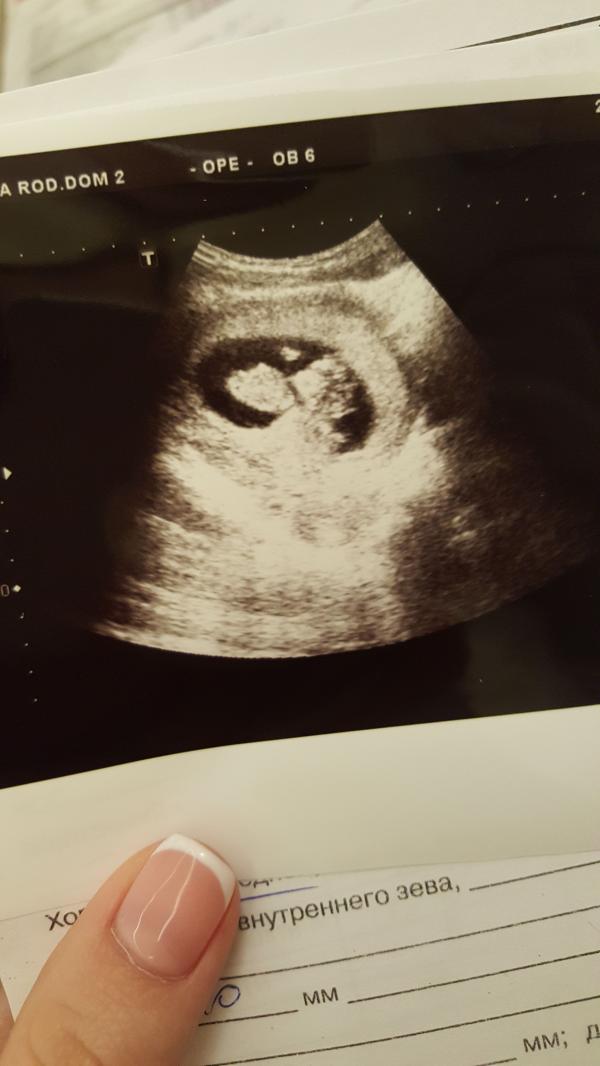

с малышонком мы познакомились❤ на Узи заходили с мужем, я снимала на телефон всё Узи со своего мониторчика !Это так круто,пересмотрела раз 10) фото тоже прикрепили к заключению. для нашего срока у нас всё хорошо. срок по узи день в день совпадает с акушерским. сердечко бьется 176 уд. в минуту, мы шевелили и ручками и ножками) ждём следующей встречи)😍